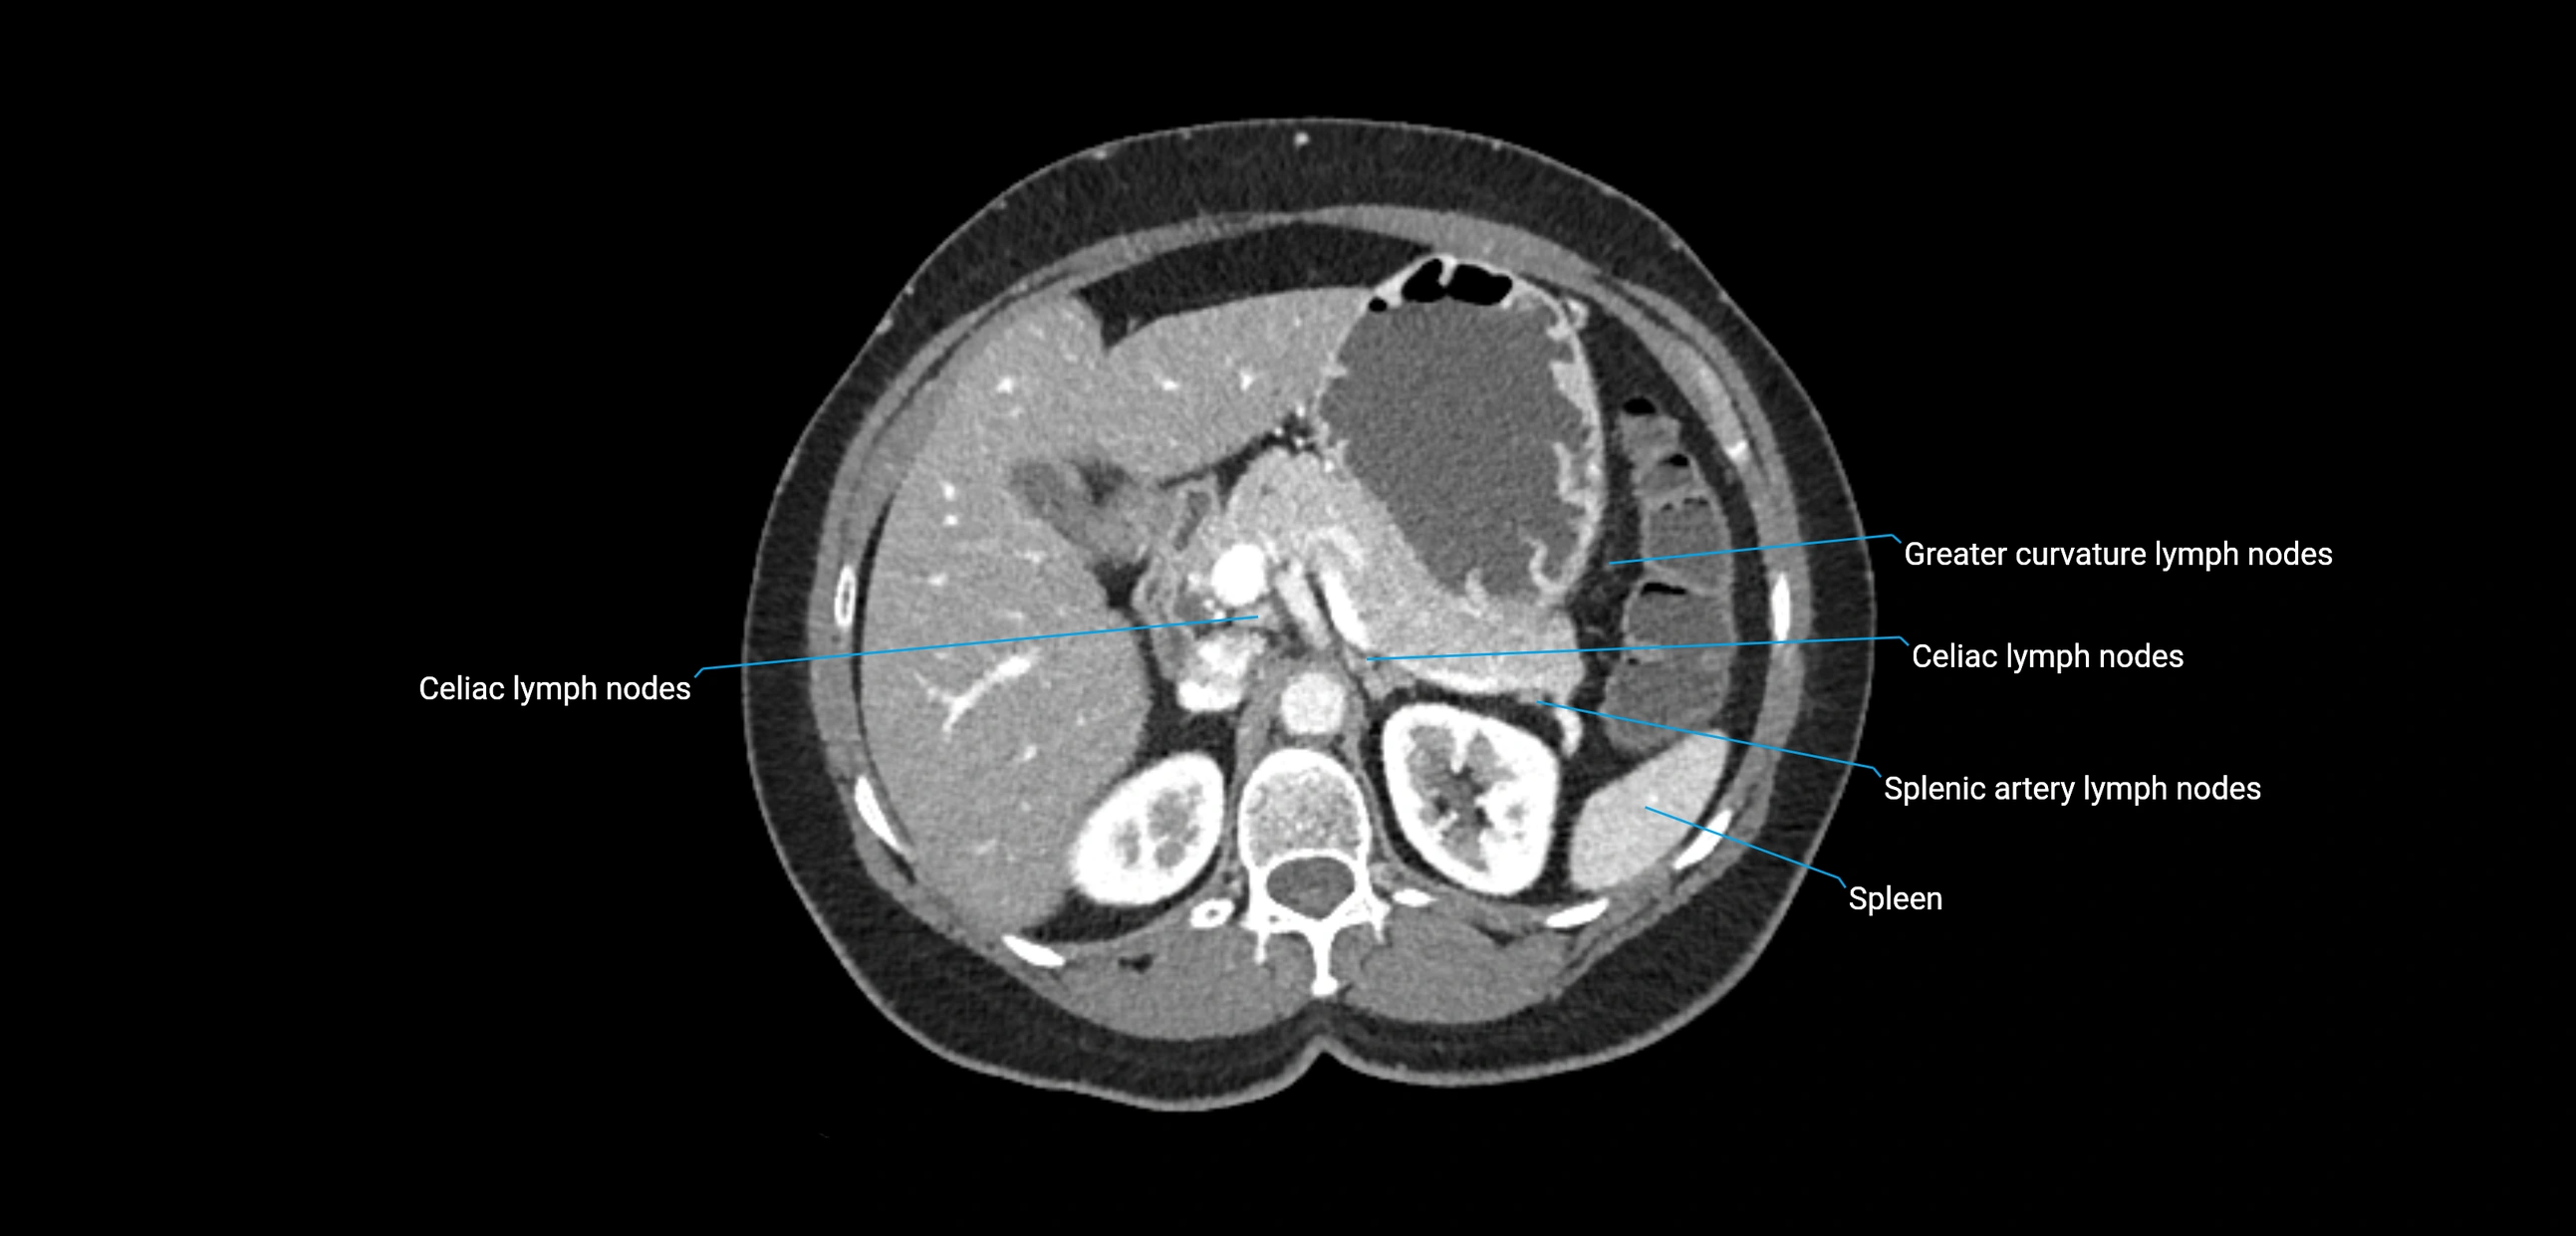

CT Appearance

CT Pre-Contrast:

• Nodes appear as soft-tissue density nodules adjacent to the aorta and IVC

• Calcification may be seen in chronic infections (e.g., tuberculosis)

CT Post-Contrast:

• Normal nodes enhance homogeneously

• Malignant nodes may show heterogeneous enhancement, central necrosis, or conglomerate formation

• Size >1 cm short axis is suspicious, though morphology and distribution are equally important